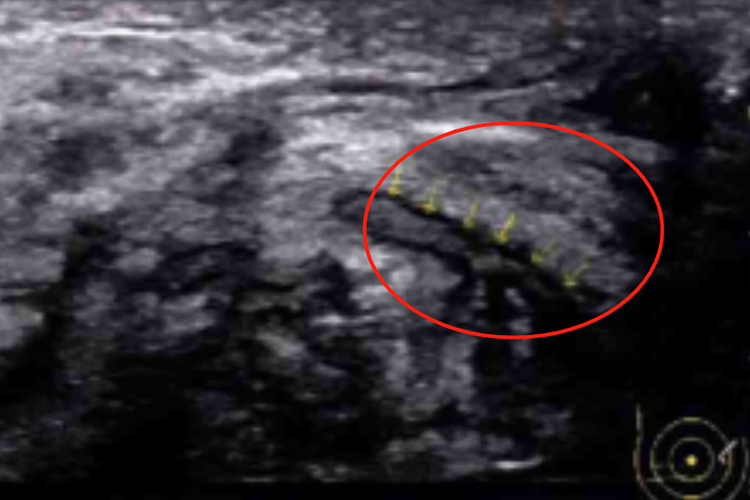

Ⅲ型:乳晕区或周围带腺体层内有实性团块,团块周边可见低回声,内部回声为均匀稍高回声或不均匀实性低回声,多可见扩张乳管内流动感低回声。